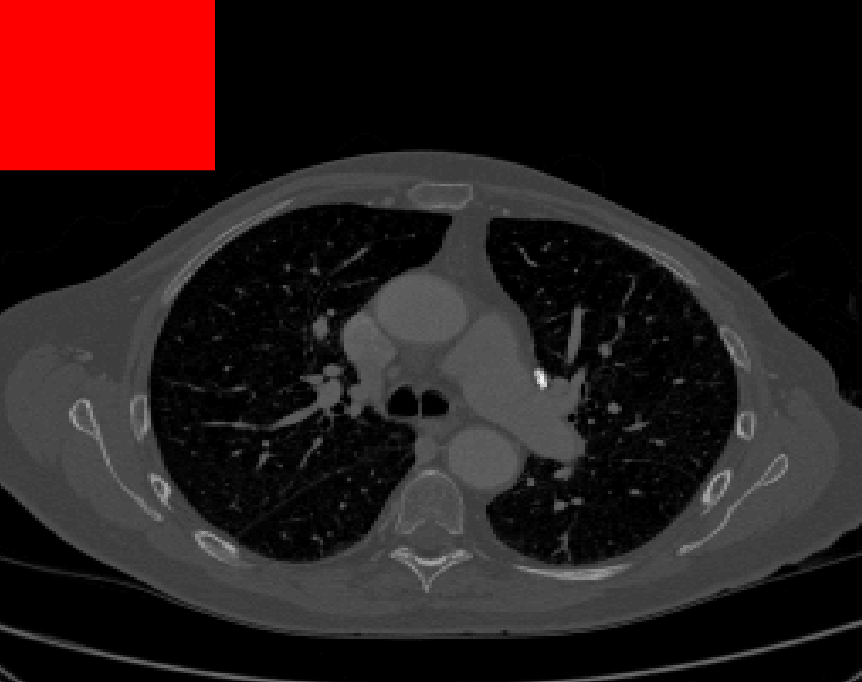

Test Images. We will perform initial tests on the images shown in Figs. 5–7. We have provided the ground truth and initialisation used for each image. Test Images 1–3 are synthetic, Test Image 4 is an MRI scan of a knee, Test Images 5–6 are abdominal CT scans, and Test Images 7–9 are lung CT scans. They have been selected to present challenges relevant to the discussion in §2. We focus on medical images as this is the application of most interest to our work. In the following we will discuss the results in terms of synthetic images (1–3) and real images (4–9). We also test the proposed approach on a larger data set of 30 CT images (a sample of which is presented in Fig. 18), comparing against existing selective methods detailed in §3.

Real Images. In Fig 12 we present results for Test Images 4–6. Here, the proposed model performs in a similar way to its competitors because these images are more typical selective segmentation problems in the sense that there is a clear distinction between the foreground and background intensities. In particular, the values in each case are: Test Image 4 , Test Image 5 , and Test Image 6 . It can be seen that the proposed model is competitive compared to previous approaches. The performance is quite poor for Test Image 5, but is arguably still the best for this challenging case. In Fig. 13 we present results for Test Images 7–9. Here the proposed model outperforms previous approaches significantly for each image. This is mainly due to the type of image considered. Specifically, the true intensities are: Test Image 7 , Test Image 8 , and Test Image 9 . The proposed model is capable of achieving results where , with other models failing completely in these cases.